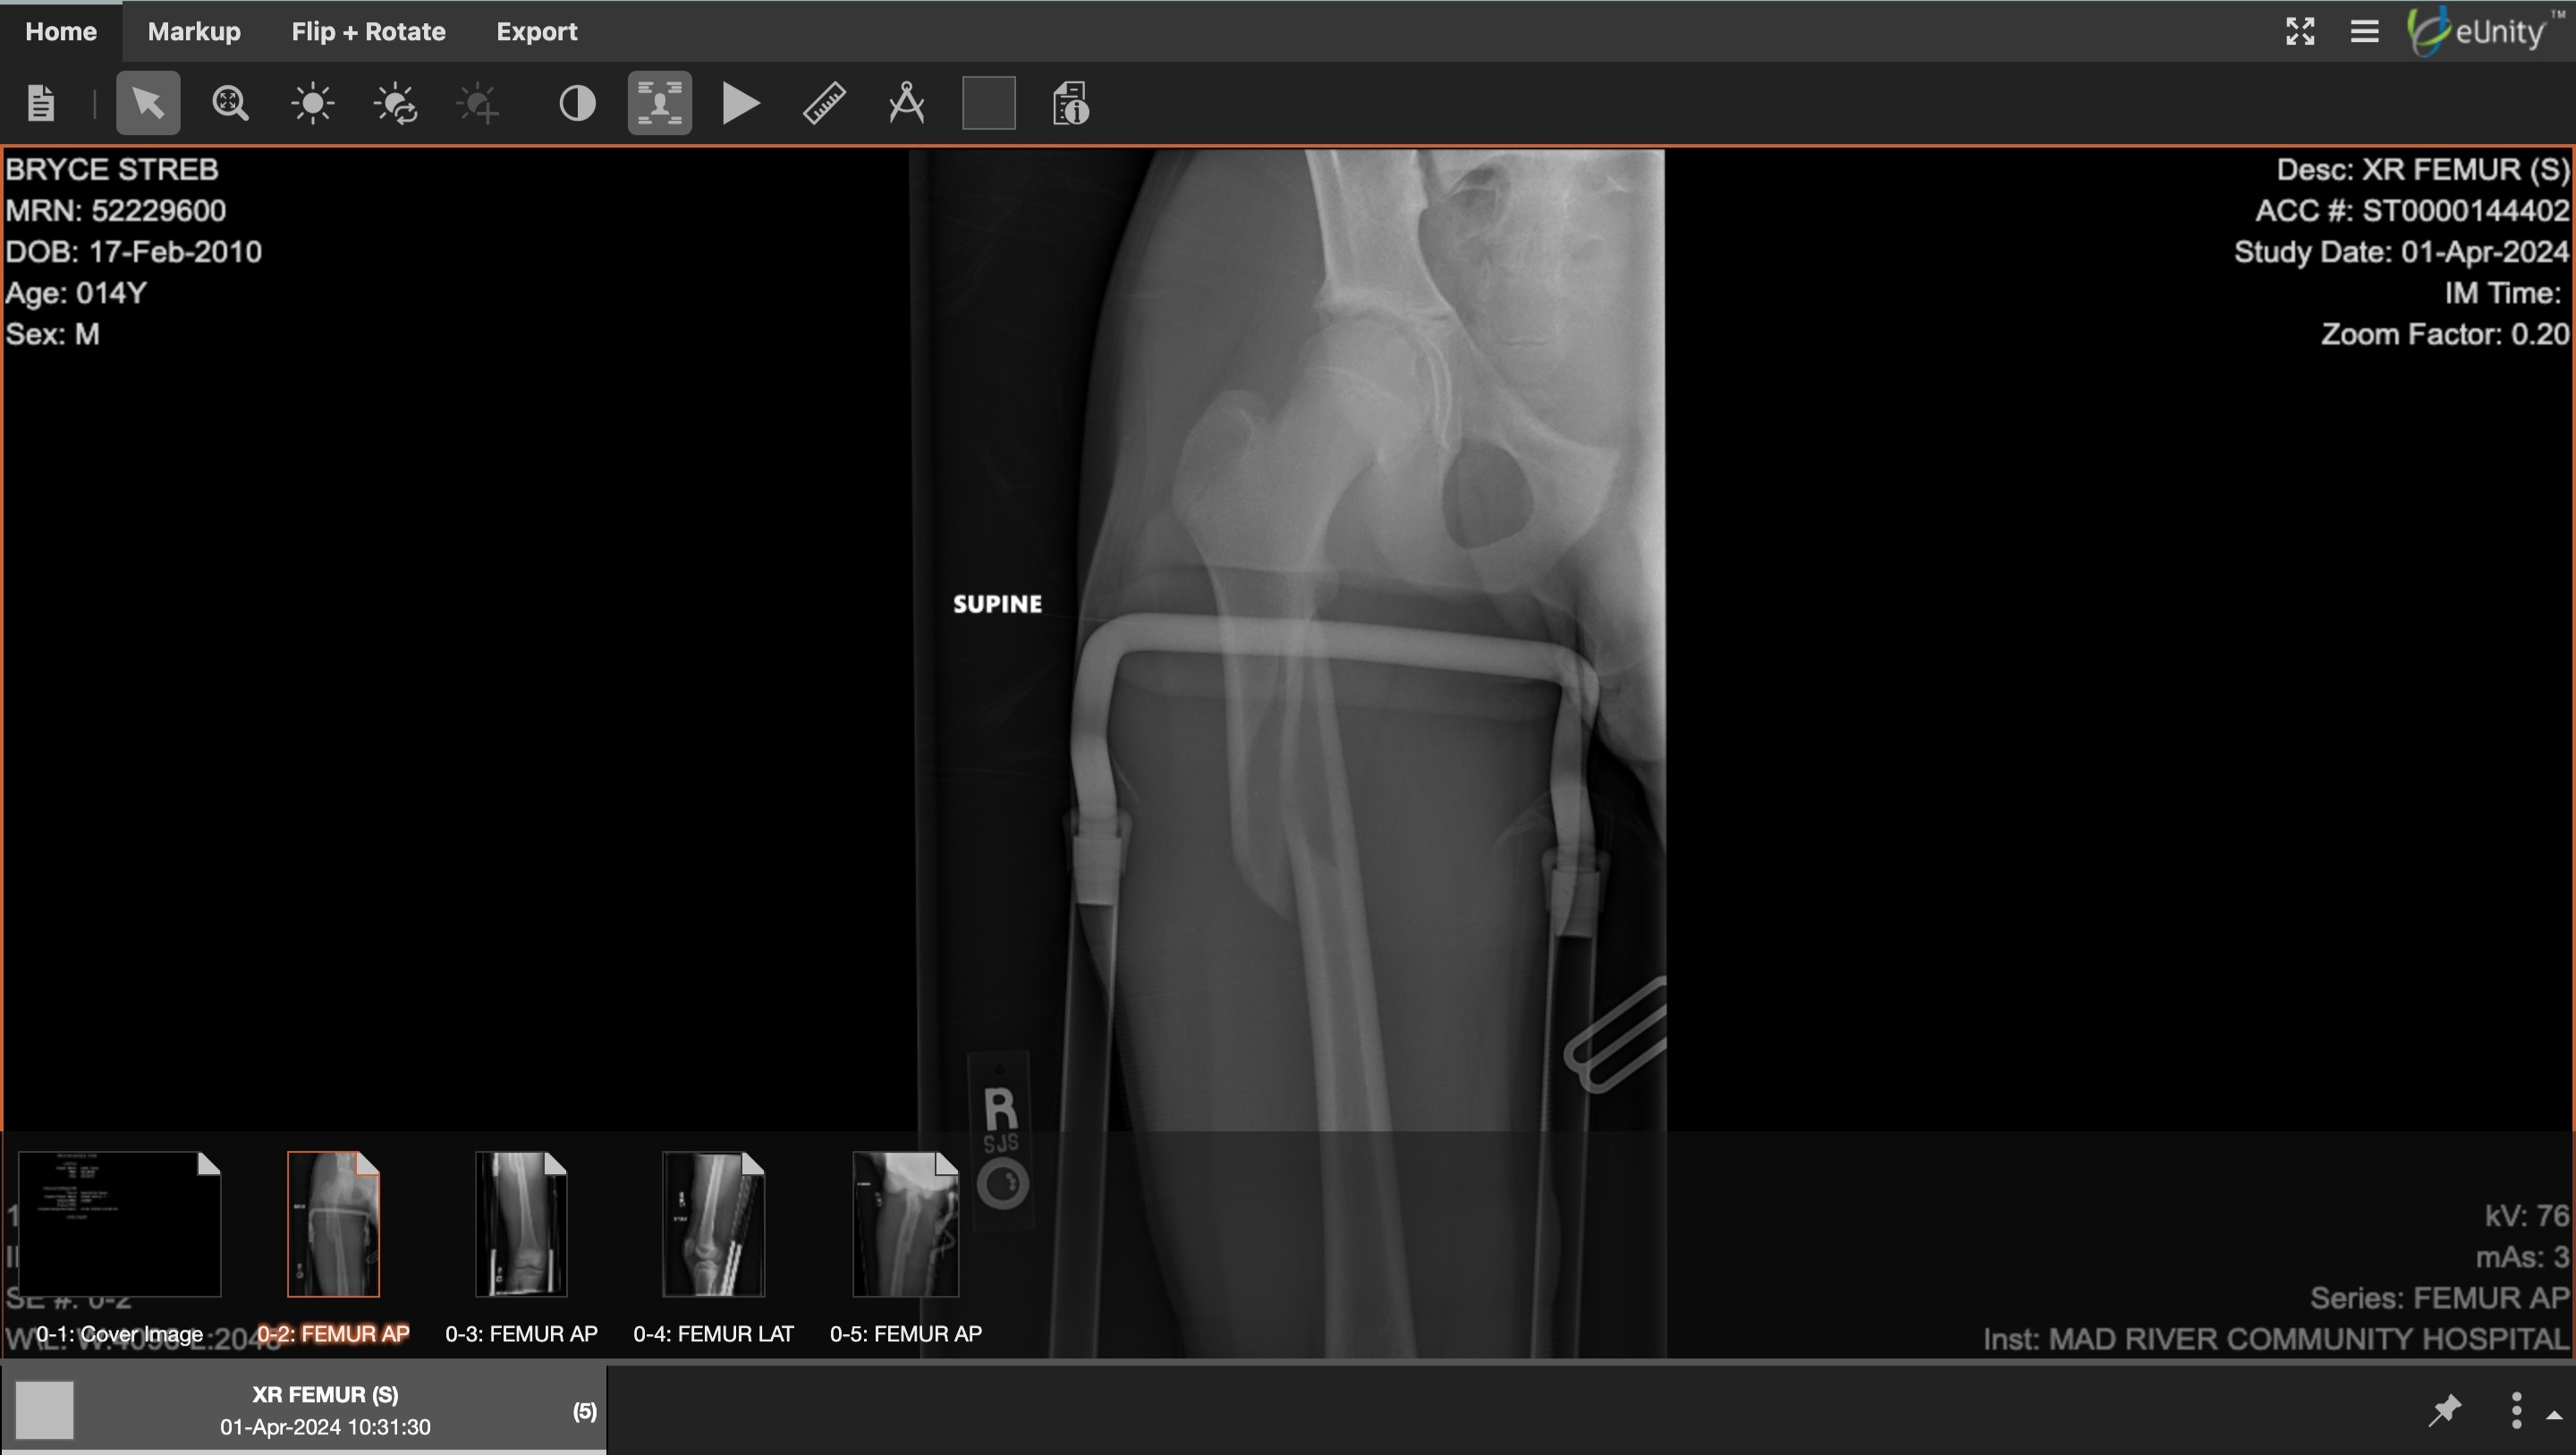

Hi I am Bryce’s mom and I am fundraising for my son who had a horrible accident while we were out of town. He was flown by Medical Plane to Children’s Hospital Oakland. Bryce has a broken femur. They did surgery and he can barely move but there has been some improvement. They put a metal rod through his femur and screws. He has been in excruciating pain.